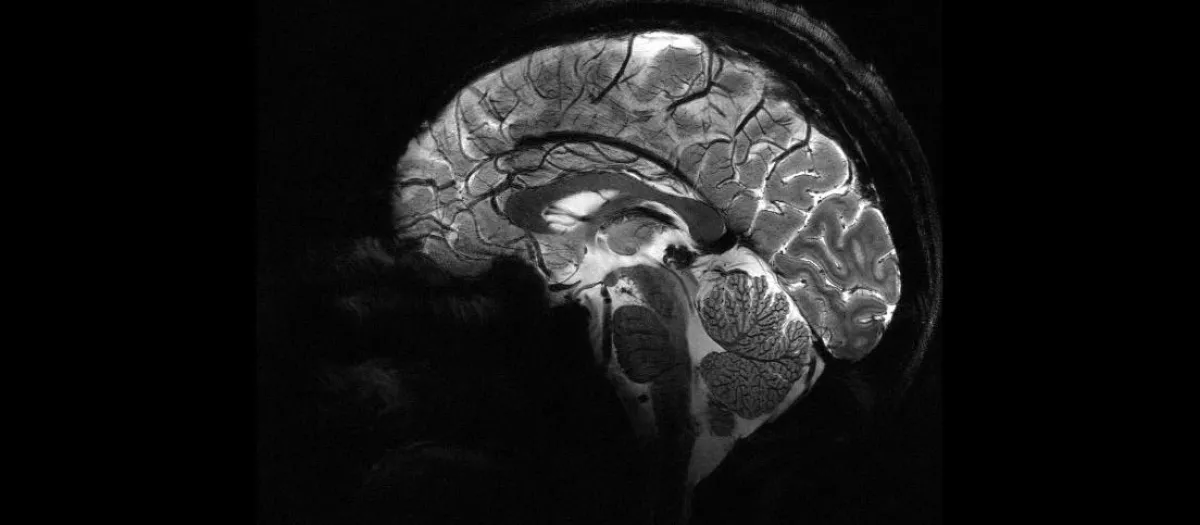

Imagen lateral del cerebroCEA

El cerebro humano es, con diferencia, el órgano más complejo de nuestro cuerpo. Su arquitectura celular y su organización en redes neuronales permiten funciones tan sofisticadas como el lenguaje, la memoria o la toma de decisiones abstractas. Pero esa misma complejidad tiene un coste: el tejido cerebral posee una capacidad de regeneración muy limitada. A diferencia de la piel o el hígado, las neuronas que mueren rara vez se reemplazan.